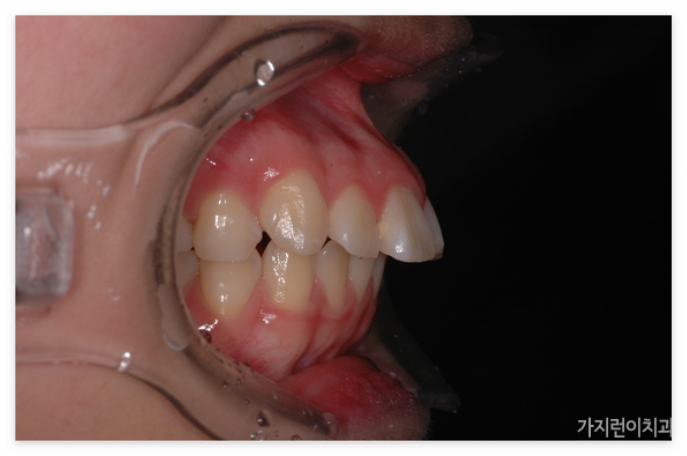

서울가지런이치과 교정과를 찾아준 환자 케이스

이 케이스는 1년 8개월의 치료기간이 소요된 환자분의 전후차이입니다. 많은 분들이 교정 후에 다시 원상태로 돌아가거나 더 심한 케이스로 변질되는 것은 아닐까 고민하시는데요. 해당 환자분은 교정 전후 차이와 7년 후의 모습까지 확인이 된 상태입니다. 환자분의 경우 잇몸뼈 돌출과 치아 돌출도 어느 정도 있는 경우여서 잇몸이 과도하게 보이는 스타일이었는데요.